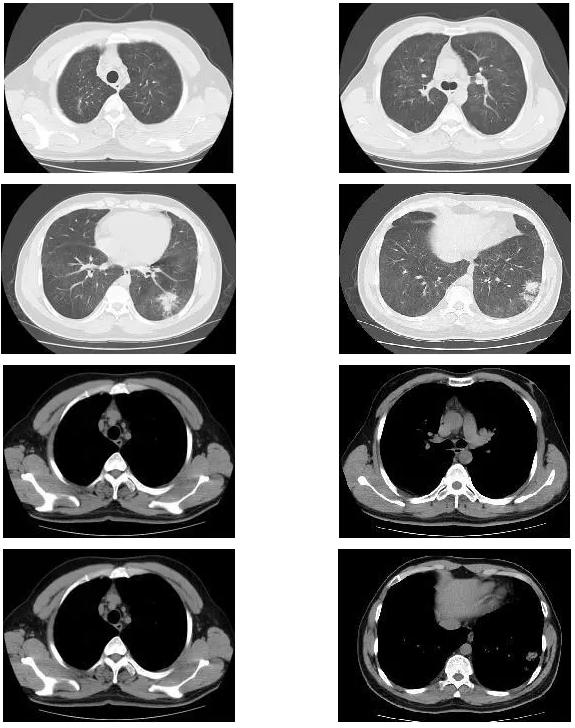

胸部CT(2017-7-31 我院门诊):两肺野弥漫磨玻璃影,性质待定;两肺上叶陈旧性病变。(如下图)

胸部CT(2018-1-18 我院门诊):两肺野弥漫磨玻璃影,较前变化不明显;新增左肺下叶基底段片状密度增高影,建议治疗后复查;两肺上叶陈旧性病变: